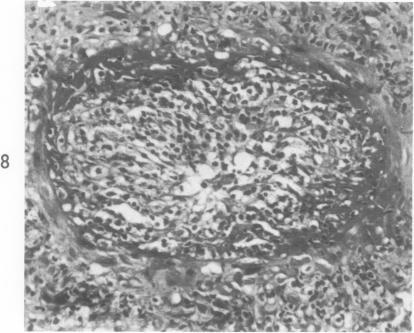

Thickening of arterial intima in rat cardiac allografts. A light and electron microscopic study.

Am J Pathol. 1971 Apr;63(1):69-84.